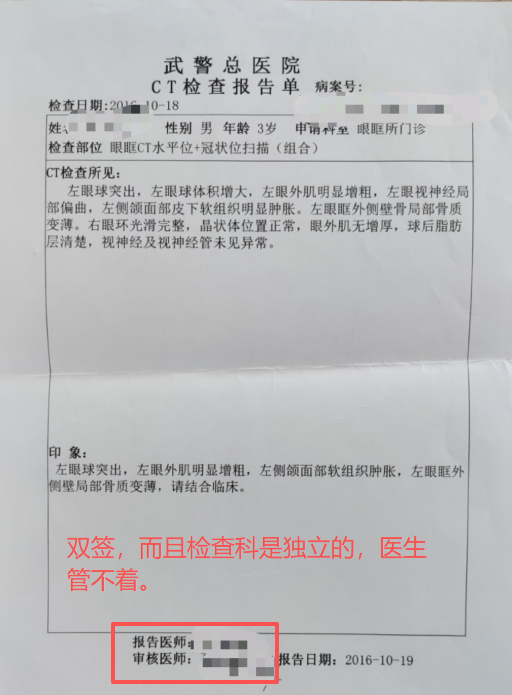

1929年10月汪精卫才从法国回香港,中医骗那是张嘴就谎啊,还张嘴就汪精卫掌实权,汪精卫1929年10月回来是支持第二次蒋桂战争干老蒋的,他还掌实权。 中医骗的特点就是张嘴就喷谎。主打一个我虽然小学3年级文化,但是够我骗文盲。 1929年,弗莱明刚刚发明抗生素,还只是实验室与论文,这就跑中国来了? 1929年,面对细菌性痢疾,西医就是没有办法治疗,所以就说治不了。1929年弗莱明虽然已经发明青霉素,但是产量感人,当时第一次使用对一个受伤感染的警察,非常有效,但是手中的一点青霉素用完了,于是警察还是shi了。 所以,西医诚实的说,没有办法治疗。 而诚实,是一种多么宝贵的品质。 因为你诚实,你说出来:我不能治疗,那么,这个疾病,就有了解决了一半。 因为你以后,所有的西医,西药,医疗器械从业者,都会想尽办法去攻克这个疾病。 而多少的绝症,曾经的绝症,因为西医的诚实,而最终研究出了真正治疗办法。 例如1921年的胰岛素。 例如1929年的青霉素。 例如1998年的伟哥。 例如2006年的HPV疫苗。 你没有。 3、西医不仅是个自然科学,他还是个管理秩序。 没有人敢保证每个西医从业者都会履行自己的诺言,所以西医除了希波克拉底誓言,还双管齐下,有一套完整的制度。 1)、一人为私,二人为公。西医的任何重大治疗与决策都是多人完成。 手术有术前评估,有术前讨论。 化验师管理体系是单独的。检查技师管理体系是单独的。甚至护士也是单独独立的。护士只是执行医生的医嘱,只是工作关系,不是上下级。护士的管理也是独立的,不归医生管理。麻醉师的管理也是独立的。 而这么多的独立,就是垂直管理,在根子上就切断医生自己一手遮天的可能。 2)、完善的文档记录。 住院病例保存30年。 住院病例需要上级医生签名。需要三级签名。修改需要红笔。 交病案后就归病案室,医生是要不回来了的。因为病案室也是独立的。 出院一定会给出院小结。需要全病历的也可以,掏复印费去病案室复印,所有的医院都允许。 所以很多中医骗张嘴就是他啥病西医看不好去找中医一看就好了,我就让他发出院小结,结果没有一个发的。我不要你隐私,你把你个人隐私涂掉,我就要病案。没有,全闪了。 等等。 在网上随便找点: |

一份最简单的住院小结,而且是格式化的,入诊、出诊、入情、治经、出情、医嘱,是格式化的,医生根本就删不掉。 送礼物 还没有人送礼物,鼓励一下作者吧 |